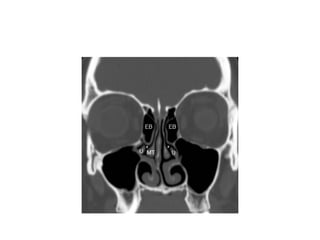

ethmoid bulla • superiorto uncinate processes. • Ethmoid bulla air cells are part of the anterior ethmoid sinuses and make up the superior border of the hiatus semilunaris. • variable pneumatization.